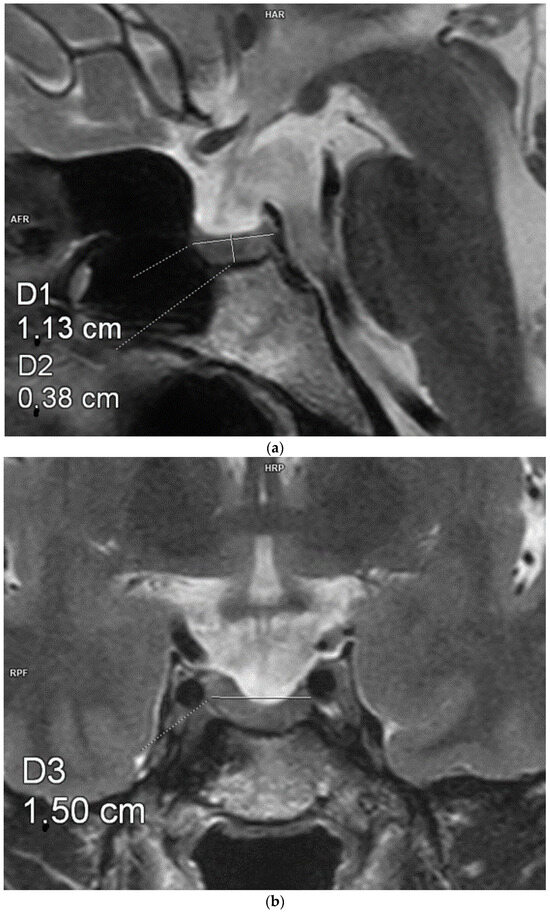

Figure 3.

Measurements of the pituitary gland. Magnetic resonance imaging, T2-weighted images in the sagittal (a) and coronal (b) planes. The craniocaudal, transverse, and anterioposterior dimensions of the pituitary gland are 3.8 mm × 11.3 mm × 15 mm.